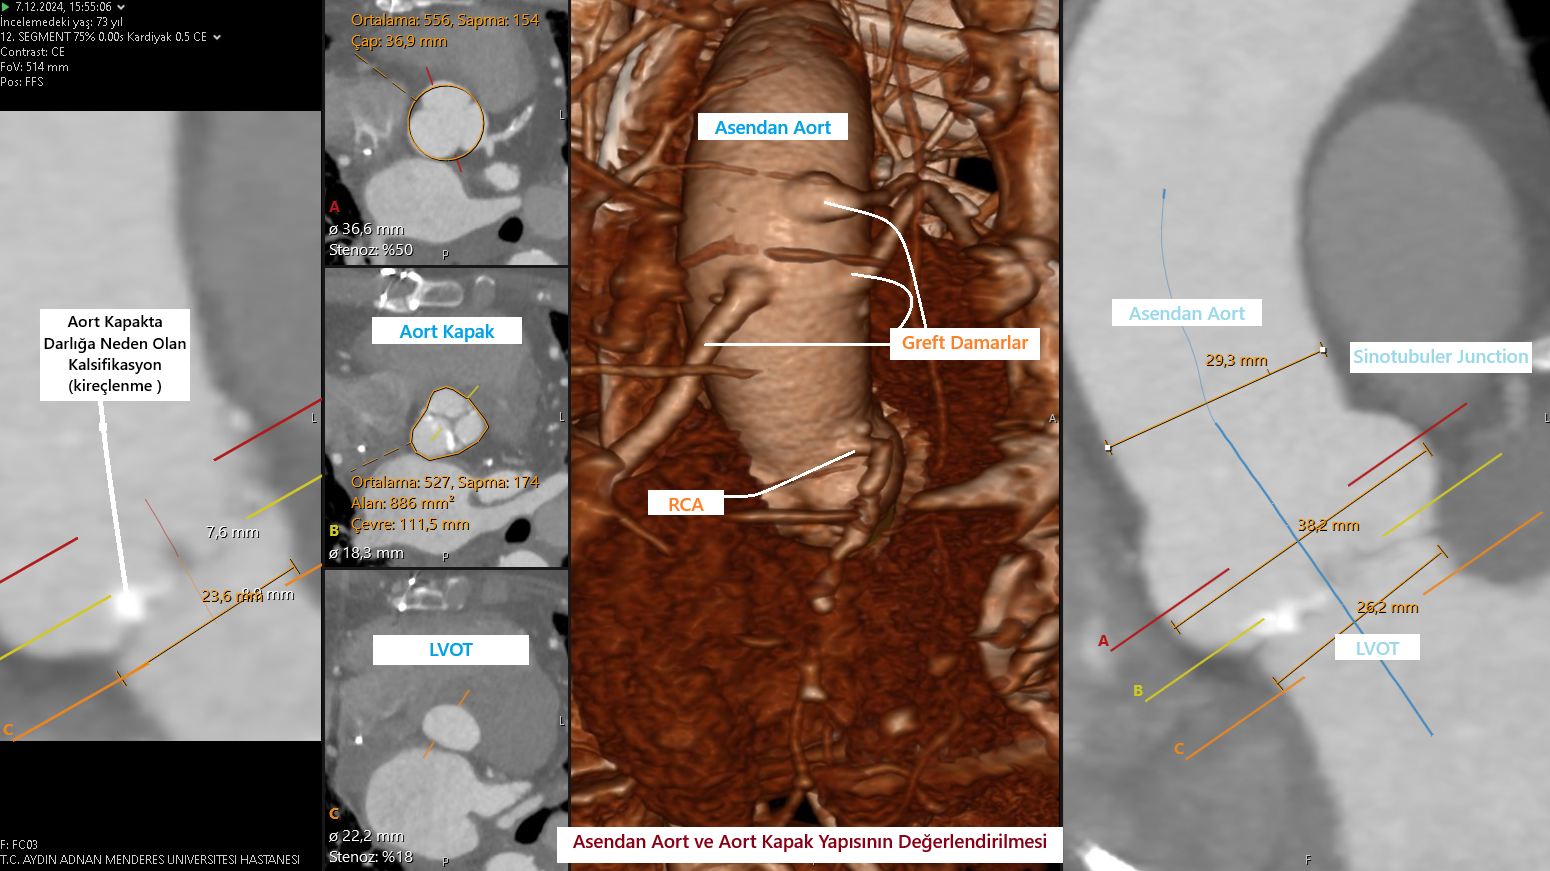

TAVI, transkateter aort kapak yerleştirme işleminin tıbbi kısaltmasıdır. Tam olarak açılamayan – kireçlenerek esnekliğini yitiren bir aort kapağının üzerine yeni kapak yerleştirerek kalbinizden aorta giden kan akımını iyileştirir ve kalbin iş yükünü ciddi oranda azaltır.

TAVI genellikle derin sedasyon ya da genel anestezi ile yapılan – kasıktaki atardamardan küçük bir kesi ile yapılan ağrısız bir işlemdir. Koroner anjiyografi veya stent işleminden kullanılan kateterlere benzeyen dar ve esnek bir tüp (katater)kasıkta bulunan atardamarınıza yerleştirilir ve kalbinizdeki aort kapağınıza ulaşılır. Bu kateter esnekliğini yitirmiş ve kireçli eski kapağınızın üstüne yedek bir kapak takmak için kullanılır. Bu katerterden geçen sistem ile ameliyata gerek kalmadan yeni biyoprotez kapak eskimiş kapağın üzerine yerleştirilir.